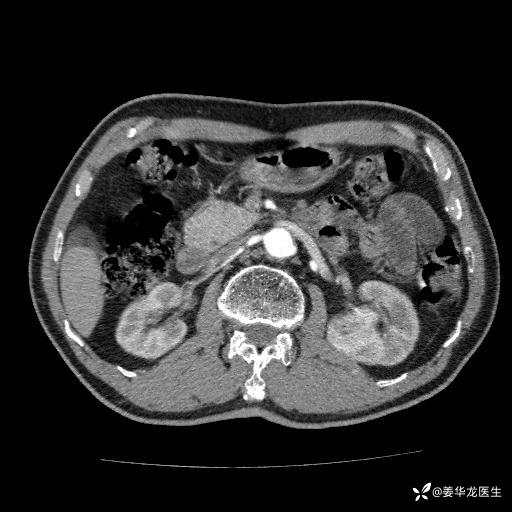

左肾中心型肾门部肿瘤39mm×34mm×36mm,右肾GFR25ml/min,部分切还是全切?

患者75岁老年男性,体重50kg,无高血压、肾病、糖尿病等基础病,检查发现左肾中心型肾门部肿瘤,右肾GFR只有25ml,无肉眼血尿,无镜下血尿。入院验血常规检查均正常,包括肾功能,肌酐102.7umol/L.

二、左肾肿瘤与左肾集合系、左肾动静脉关系密切,左肾部分切除术可行吗?成功率有多大?成功部分切后,肾功能还有多少?